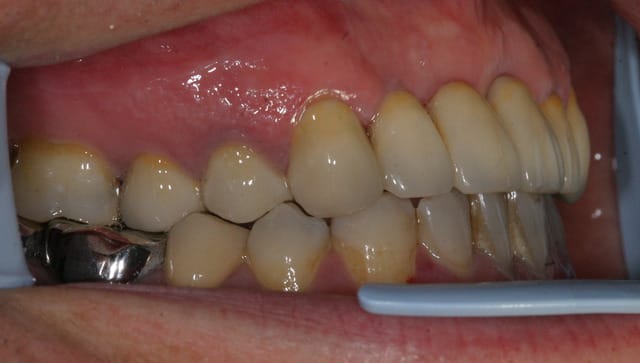

tient un boulot ou il y a un peu de tout.

bridge antérieur , car la pose d'implants nécessitait de la reconstruction trop importante, endo couronne sur les molaires mandibulaires par manque de hauteur, onlay. implants à la mandibule.

A noter les 2 PM maxillaires qui comportaient

chacune 3 canaux.